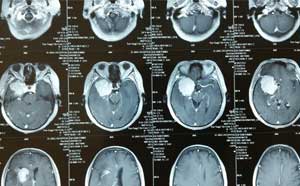

厚朴方舟是专业的出国看病医疗服务机构,为患者整合美国日本及国外脑膜瘤治疗权威的排名靠前的医院和专家资源。结合患者的病情,对患者病情进行诊断,分期治疗方案。对患者提供脑膜瘤相关疾病出国治疗申请服务、新的治疗方法技术、治疗药品药物等相关知识。

关于脑膜瘤生存率的问题,一直是脑膜瘤患者较为关心的问题,厚朴方舟医学顾问今天根据美国国家癌症协会有关资料,为您总结了脑膜瘤生存率的有关问题,想知道的话就往下看吧! 1.脑膜瘤

脑膜瘤患者或者关注脑膜瘤相关知识的人群会遇到一个词叫小脑膜瘤,厚朴方舟医学顾问今天为大家科普一些与小脑膜瘤有关的内容,包括小脑膜瘤是什么?小脑膜瘤治疗方案等内容,一起看看

大部分脑膜瘤生存率较高,但是如果不定期检查,就容易出现复发的情况,那么,脑膜瘤复发后怎么治疗呢?厚朴方舟医学顾问今天为大家回答这个问题,希望对您有所帮助。 一、脑膜瘤复发治

脑膜瘤手术治疗是主要方法,那么手术治疗之后呢?脑膜瘤术后还需要进行哪些治疗呢?厚朴方舟医学顾问今天为您总结一些脑膜瘤术后治疗方法,希望对大家有所帮助。 一、脑膜瘤术后治疗方

脑膜瘤患者的主要治疗方法为手术治疗,那脑膜瘤患者想不想知道手术治疗的效果如何呢?一起跟随厚朴方舟医学顾问来探讨一下脑膜瘤手术治疗效果吧! 一、脑膜瘤手术治疗方法 通常,脑膜瘤

脑膜瘤大多数情况下都是良性的,但是也有少数是恶性脑膜瘤,那么恶性脑膜瘤治疗办法是什么呢?有没有治疗恶性脑膜瘤效果较好的方法呢?不要急,厚朴方舟医学顾问今天为大家答疑解惑。

多数情况下,老年人患有脑膜瘤比去年轻人患有脑膜瘤要更复杂一些,因为部分老年人身体素质较差,治疗相对困难,那么,老年人脑膜瘤治疗方法有哪些呢?厚朴方舟医学顾问今天与您聊一聊

脑膜瘤后遗症一般包括:突眼、眼睑下垂、头痛、记忆力减退等等,严重的则可能出现瘫痪、脑疝等,有可能会危机生命,因此,脑膜瘤后遗症治疗十分重要,那么脑膜瘤后遗症怎么进行治疗

脑膜瘤治疗的关键不仅仅在于医生的专业性,患者也应该具备相关医学知识,今天厚朴方舟医学顾问为您科普脑膜瘤治疗方法有几种,希望对大家有所帮助。 一、脑膜瘤治疗方法 根据美国癌症